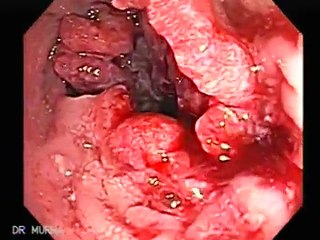

- If you are experiencing rectal bleeding, you should definitely have it checked to ensure it's not colon cancers. A specialist can determine if the rectal bleeding is caused by cancer or the lesser intestinal conditions involving hemorrhoids or diverticulitis. A specialist should be able to provide you with the proper treatment if it is actually a hemorrhoid case or a different condition.